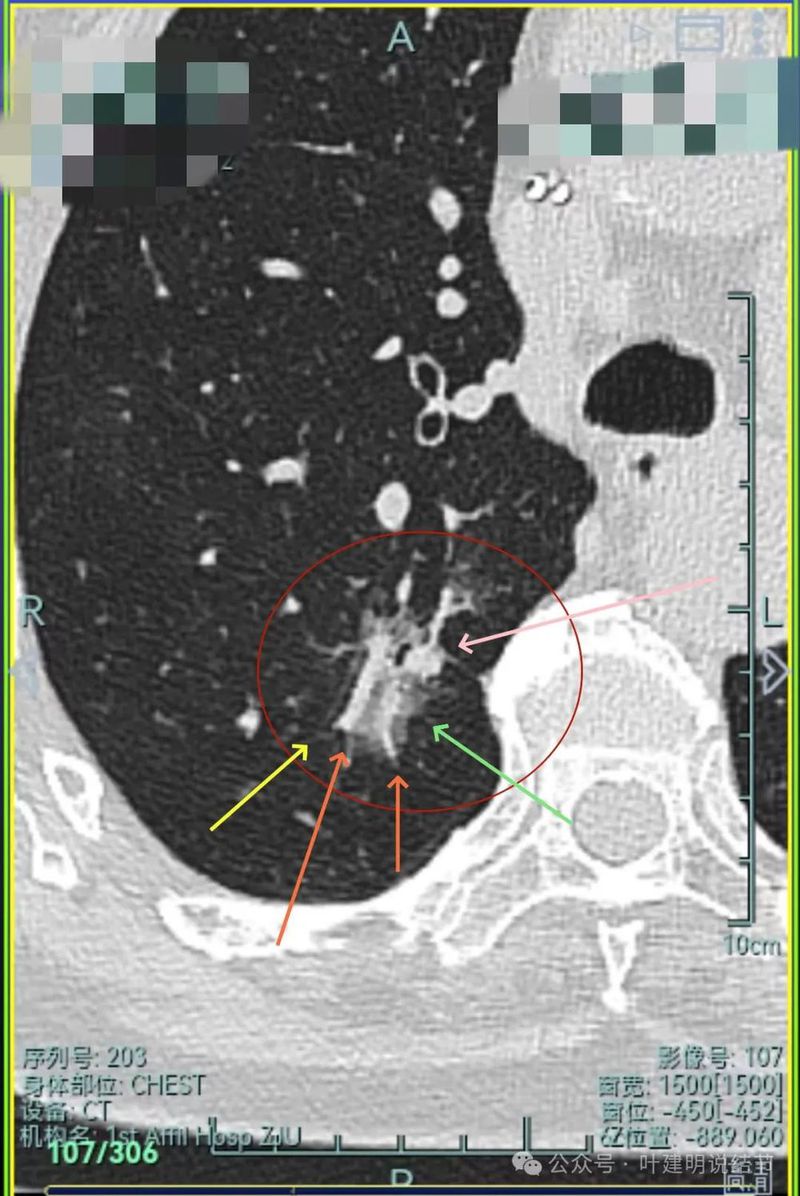

主病灶连续层面展示分析:

有明显血管进入,表面分叶,边缘不平,整体轮廓清。

边缘毛刺、表面不平、灶内偏实性成分、分叶明显,整体轮廓与瘤肺边界较为清楚。

灶内细支气管扩张、边缘毛刺较为锐利、有明显磨玻璃成分,磨玻璃成分的瘤肺边界清楚,病灶分叶明显。

灶内密度杂乱不均,内有小空泡征,表面不平。

灶内血管增粗穿行、磨玻璃成分明显,轮廓较清。

血管进入,磨玻璃成分,支气管扩张,边缘不平。

典型混合密度病灶,中间部分密度高偏实性,外围部分磨玻璃密度,两者之间交错存在,说明偏实性部分有侵袭性。磨玻璃成分与正常肺组织之间界限清楚,表面分叶,部分边缘毛刺,整体轮廓清。是非常符合恶性的影像表现。

灶内磨玻璃成分明显,并有异常增粗血管僵硬穿行于病灶内,支气管有扩张通气征,瘤肺边界清楚,实性成分明显。